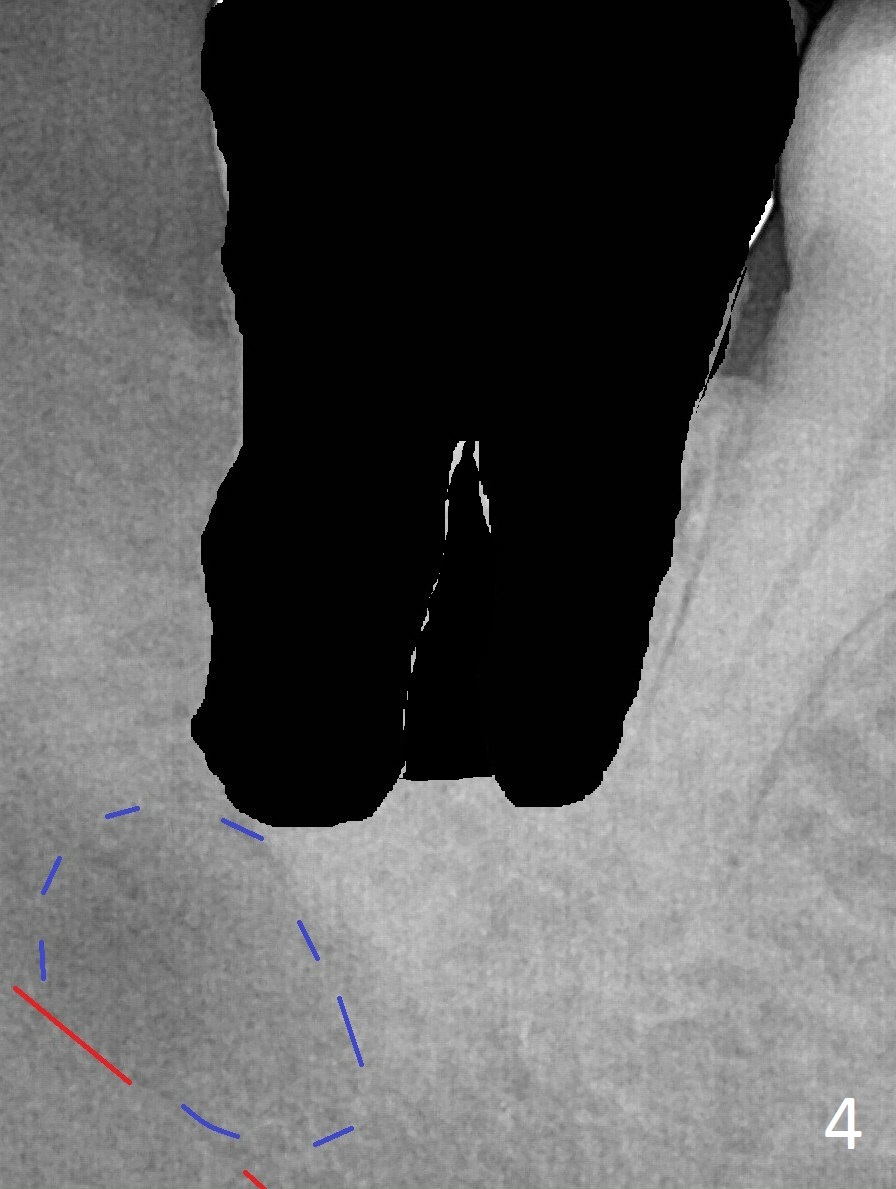

A 45-year-old woman presents to clinic with swelling and pain from the lower right posterior region. The tooth #32 is fully bony impacted. The distolingual gingiva of #31 is erythematous with deep pocket. The tooth is sensitive to percussion. Preop panoramic X-ray shows a radiolucent lesion between #31 and #32 (Fig.1 blue dashed line). Initial impression is infection from #32. Extraction of the latter turns out to be difficult. Purulent discharge is coming from underneath the coronal portion of the tooth. Curettage of the radiolucent lesion leads to hemorrhage. The curettage is not aggressive because of the underlying Inferior Alveolar Canal (red dashed line). Following copious irrigation, a 10x20 mm Osteogen plug is inserted into the socket with incision closure. Postop PA reveals that the roots the teeth #31 and 30 approximate to each other (Fig.2 R). In case the tooth #31 needs to be removed (Fig.3 black area), osteotomy for immediate implant will be established in the middle of the septal stump (Fig.5 red arrow) after removal of the coronal septum (Fig.4). CBCT may be necessary for determination of the osteotomy depth.